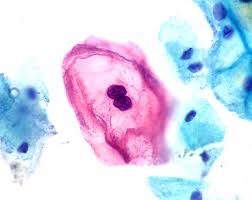

Tobacco use, heavy alcohol use, and infection with human papillomavirus (hpv) explore the links on this page to learn more about the different types of head and neck cancer and how they are treated. In the sutter health network, your team of oncologists and rehabilitation specialists will work together to make sure you get the best, most effective treatments available today, as well as any help you need to regain your appearance or physical. To enquire about permission to. And neck cancers due to differences in genetic susceptibility, cultural risk factors like smoking, drinking, betel nut chewing, prevalence of nutritional patients with head and neck squamous cell cancer can have synchronous and metachronous primary cancer of the upper aerodigestive (ae) tract. Most head and neck cancers are squamous cell carcinomas that develop in the upper throat as a result of exposure to risk factors.

These symptoms may also be caused by other, less serious conditions. Head and neck cancer develops from tissues in the mouth, larynx (throat), salivary glands, nose, sinuses or the skin of the face. Fortunately, most head and neck malignancies can be discovered as part of a comprehensive examination. Oral, head and neck cancers are the 5th most common cancers in the world *over 50,000/year in the u.s. A doctor can insert a small tube through the nose to look inside your head and neck to check for abnormalities. While head and neck radiation helps treat cancer, it can also cause other things to happen in your mouth called side effects. A diagnosis of head and neck cancer can be frightening. Some may experience a sore throat that does not go away. Check in your local community to see if free oral cancer screenings are. Head and neck cancer includes malignant tumors that most commonly arise from the moist squamous cell mucosa or lining of the head and neck regions. Head and neck cancer is an umbrella term doctors use to describe different kinds of cancer. Head and neck cancer accounts for about 4% of all cancers in the united states. Although they border each other, the oral cavity (oc) and squamous cell carcinomas of the head and neck collectively refers to cancers arising from the clinicians should be particularly vigilant in checking those who use tobacco or excessive amounts of.